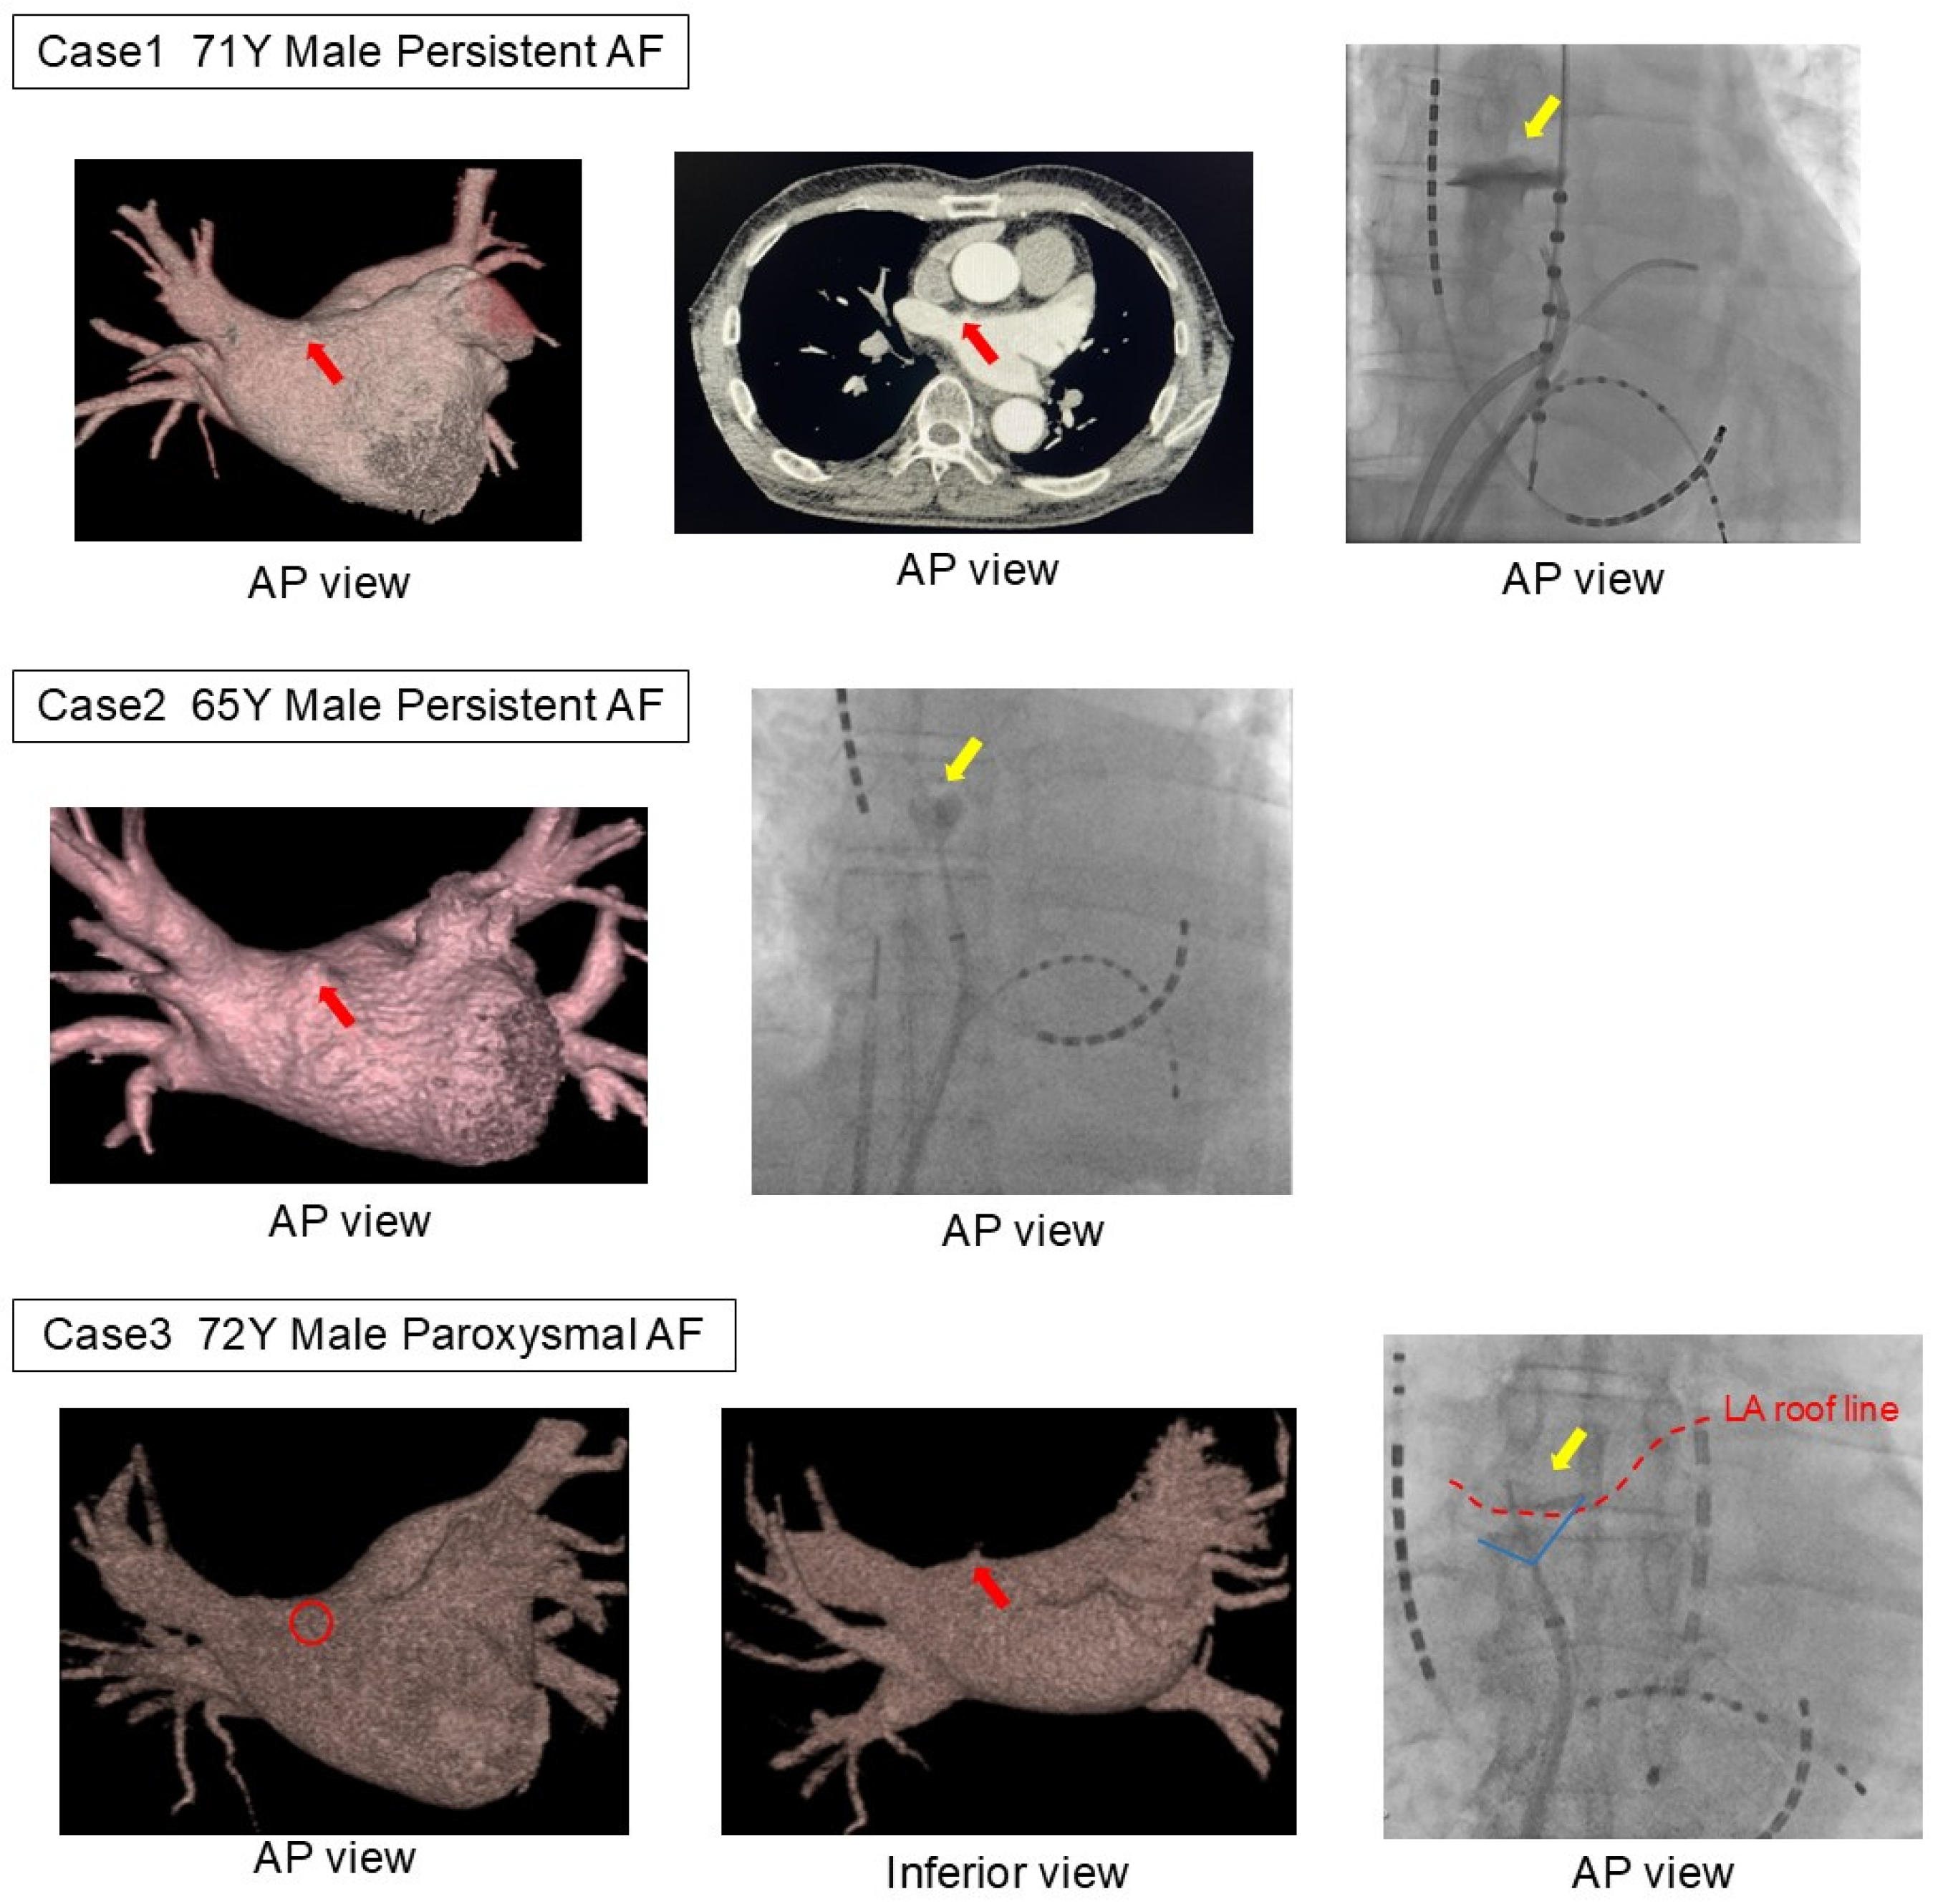

Among the mechanical complications in the LAD group, three cases were cardiac perforations caused by LADs, while the remaining case was a cardiac tamponade due to a steam pop during the creation of the cavo-tricuspid isthmus block line. All LAD-related mechanical complications occurred during the first AF catheter ablation, with the LAD consistently localized in the anterior region of the right superior pulmonary vein (Figure 2).

The first case involved a 71-year-old male undergoing his initial ablation of persistent AF, with a planned BOX isolation using radiofrequency catheter ablation. Pulmonary venography was first performed in the left pulmonary vein using an 8.5Fr long sheath and a 5F angiographic catheter before advancing the ablation catheter into the left atrium. While rotating the sheath clockwise to insert the catheter into the right superior pulmonary vein, the catheter tip inadvertently entered the LAD, causing contrast extravasation. As hemodynamic stability was maintained without a rapid pericardial effusion accumulation, the procedure was continued. Due to the risk of catheter entrapment, radiofrequency ablation was switched to cryoballoon ablation. The contrast pooling resolved relatively early during the procedure. The second case involved a 65-year-old male undergoing his first ablation of persistent AF, with a planned cryoballoon ablation. Similar to the first case, pulmonary venography was performed using an 8.5Fr long sheath and a 5F angiographic catheter. While rotating the sheath clockwise to insert the catheter into the right superior pulmonary vein, contrast extravasation from the diverticulum was observed. Hemodynamic stability was maintained, and the procedure was successfully completed as planned. The third case involved a 72-year-old male undergoing his first ablation for paroxysmal AF, also with a planned cryoballoon ablation. As in the previous cases, contrast extravasation from the diverticulum occurred at the same procedural stage. Hemodynamic stability was maintained, and the procedure proceeded as planned.

All three patients with complications reported in this study had LADs in the anterior region of the right superior pulmonary vein, which is the typical predilection site. In all cases, extravasation was observed during pulmonary venography performed prior to the pulmonary vein isolation with a 5F angiographic catheter, wedged into the LAD. Considering the anatomical relationship from the septal puncture point, catheter manipulation around the anterior region of the right superior pulmonary vein, the most common site for an LAD, is more likely to result in mechanical complications, as the catheter comes into perpendicular contact with the LAD.

Figure 2. Three patients with LAD-related complications. In all three cases, extravasation was observed during pulmonary vein angiography using an angioburman catheter. In all cases, an LAD was found on the anterior side of the right superior pulmonary vein, the common site of the LAD. The catheter had inadvertently entered the diverticulum during contrast injection immediately after transitioning from angiography of the left pulmonary vein to that of the right pulmonary vein. The red arrow indicates the left atrial diverticulum on the CT image, the yellow arrow points to the extravasation of contrast observed in the fluoroscopic image, and the red dashed line represents the roof line of the left atrium. LA, left atrium; LAD, left atrial diverticulum.